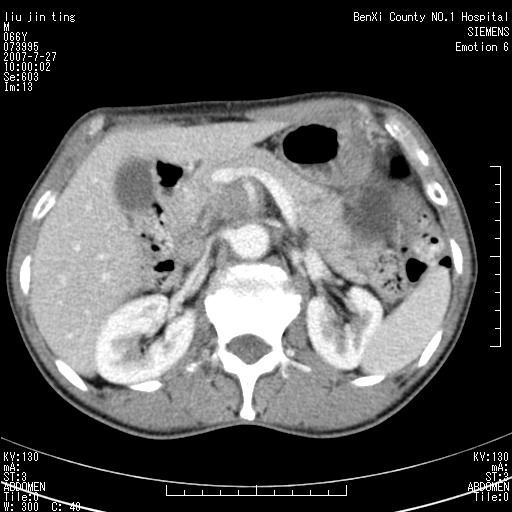

腹痛,背痛,无恶心呕吐,不黄,彩超示胰腺钩癌,ct扫描病灶平扫30-40hu,增强后动脉期40--60hu,静脉期50-68hu,真的是钩突上的么?您要试一试么?

静脉期

沿着肠系膜上动脉呈匍匐性生长的软组织肿块,形态不规则,包绕肠系膜上动脉,呈明显强化,考虑来源于肠系膜的恶性肿瘤

沿着肠系膜上动脉呈匍匐性生长的软组织肿块,形态不规则,包绕肠系膜上动脉,呈轻-中度强化,考虑来源于肠系膜的恶性肿瘤。